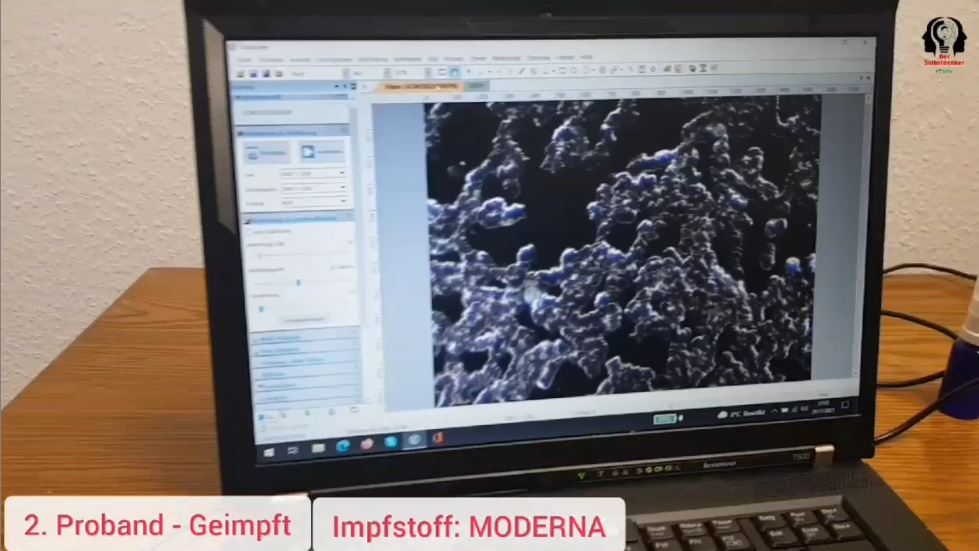

Impfschäden Schweiz Coronaimpfung,

[02/12/2021 11:07 A.M.]

https://t.me/Impfschaden_Corona_Schweiz/32666

Eine neue Meldung:

Ein Arzt in Sachsen hat am Montag 29.11. in seiner

Praxis zusammen mit einem Naturheilpraktiker und dem

Kanalbetreiber von “Der Selbstdenker” eine vergleichende

Blutuntersuchung von jeweils 4 Geimpften und 4

Ungeimpften unter dem Dunkelmikroskop

durchgeführt. Jedes Detail wurde gefilmt, um Transparenz

und Glaubwürdigkeit zu demonstrieren.

Ergebnis: Die Struktur und Beweglichkeit der

Blutkörperchen weisen signifikante Unterschiede auf; so

sehr dass es einem schlecht wird.

Bei den Ungeimpften haben die Blutkörperchen eine runde

und abgegrenzte Struktur, die je nach Lebensweise

Unterschiede aufzeigt.

Bei den Geimpften mit Biontech und Moderna sieht man im

Dunkelmikroskop, wie die Blutkörperchen zu einem

Breiartigen Cluster zusammen gepappt sind und fast keine

Beweglichkeit mehr zeigen. Die Aufnahme von Sauerstoff

ist damit signifikant reduziert und wenn sich die

Blutkörperchen nicht mehr bewegen können, sind auch die

Aufgaben im Organismus nicht mehr möglich. Der Arzt sagt

im Video (lange Version), dass damit auf Dauer ein

Sauerstoffmangel in sämtlichen Organen zu erwarten ist.